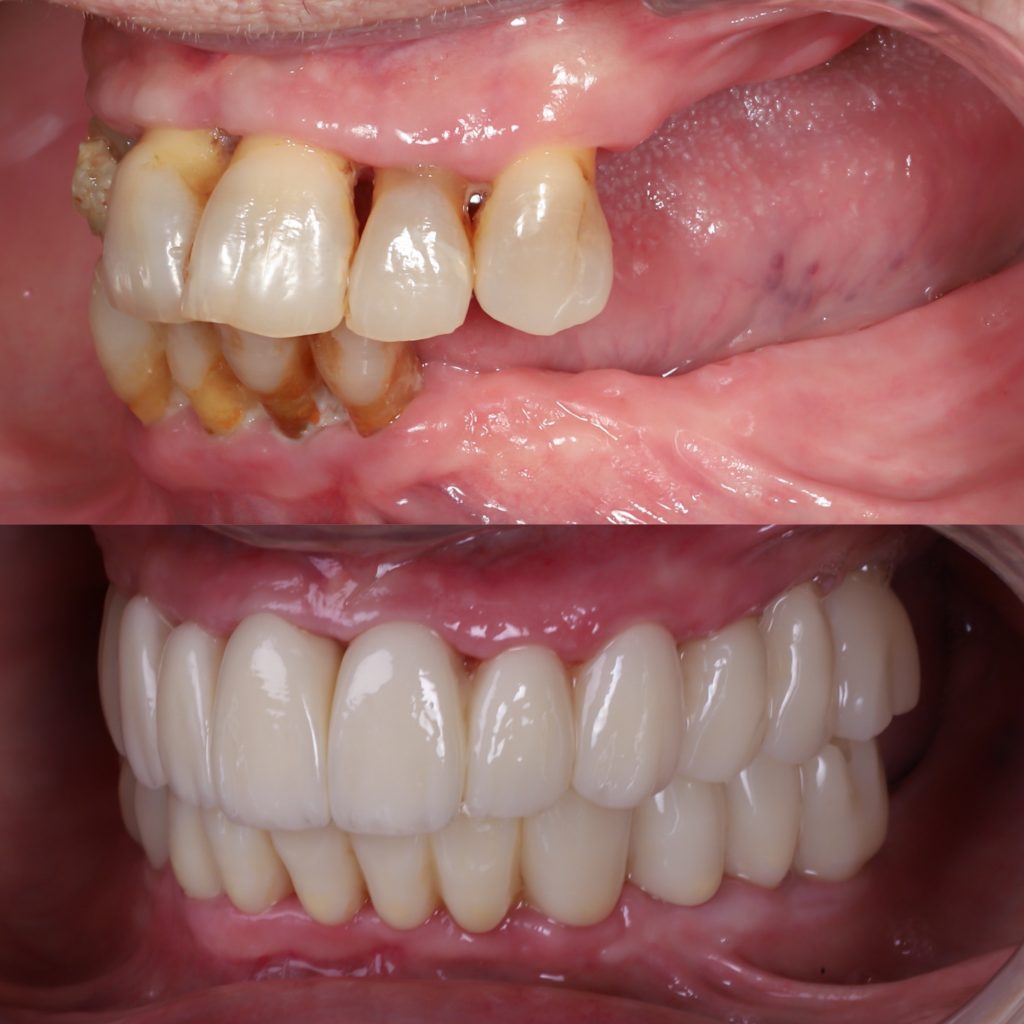

Historias de transformación

Si alguna vez te han dicho que tu caso no tiene solución, en Alejandro Prieto Dental desafiamos los límites de la odontología para ofrecerte la respuesta que estabas buscando.

Visualizar la transformación

Los cambios de imagen de la sonrisa favorecen mejoras cuidadosas y matizadas, para obtener resultados naturales que garanticen el equilibrio general y la armonía facial.